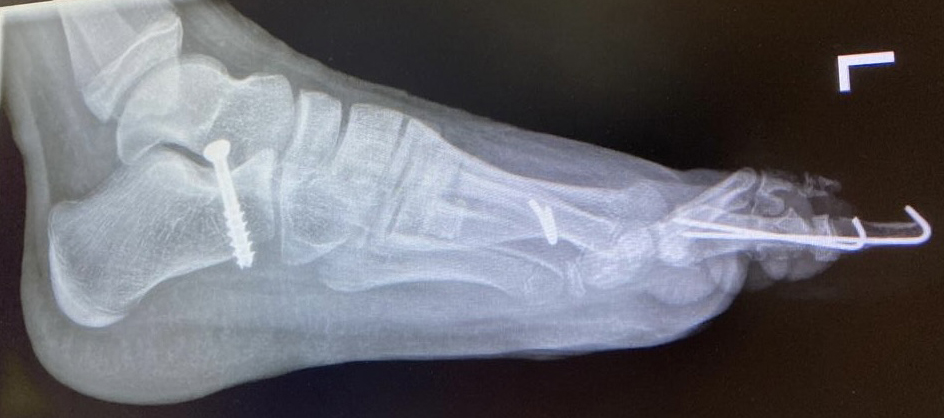

Calcaneus-Osteotomie

Die minimalinvasive Calcaneusverschiebeosteotomie bietet eindeutige Vorteile gegenüber dem offenen Verfahren, sodass wir bei Kindern und Jugendlichen nahezu keine offene Verschiebeosteotomie mehr durchführen. Am Calcaneus liegt die offene Wachstumsfuge dorsal. Bei der Durchführung müssen Schenkel der V-förmigen Osteotomie daher etwas steiler angelegt werden, in einem stumpfen Winkel (siehe Abb. 3 a-j). Für die Osteotomie liegen unsere Patienten auf dem Rücken und der BV wird für die exakte Seitaufnahme eingestellt. Der Fuß lagert auf einem hohen OP-Kissen und die Osteotomie kann bequem mit einem langen Kirschner-Draht und einem sterilen Stift angezeichnet werden (Abb. 15).

Damit lässt sich im Verlauf Röntgenstrahlung für die jungen Patienten vermeiden und die minimalinvasive Osteotomie kann sicher durchgeführt werden. Anschließend erfolgt die Verschiebung oder Impaktion. Ist ein Gleiten nach plantar oder cranial des distalen Fragmentes erwünscht, wird die Osteotomie schräg ohne V-Form entweder verlängernd oder verkürzend durchgeführt (Abb. 16).

Durch den knöchernen Defekt der Fräse gelingt die Verschiebung bei der minimalinvasiven Osteotomie im Fall von strukturell festen Klumpfüßen mit starkem Zug der verkürzten Achillessehne oder bei einer fixierenden spastischen Grunderkrankung einfacher gegenüber dem offen Verfahren. Ein weiteres Plus bei hyperaktiven Weichteilen ist die Vermeidung der ungewollten Cranialisierung des dorsalen Fragmentes durch die V-förmige Osteotomie (Abb. 16).

Die minimalinvasive Calcaneusverschiebeosoteotomie kommt somit in der Versorgung von kindlichen und jugendlichen Fußdeformitäten in einem weiten Erkrankungsspektrum zum Einsatz (Abb. 16):

- Plattfuß – Varisation

- Klumpfuß residual – Valgisation und ggfs. Cranialisation sowie Impaktion

- Klumpfuß überkorrigiert – Varisation und ggfs. Plantarisierung

- Hohlfuß – Cranialisation und ggf. Valgisation (alternativ minimalinvasive Austin-Osteotomie)

Abb. 16 a-f: Varisation einer valgischen Calcaneusstellung bei Knick-Senk-Fuß mit V-förmiger Osteotomie axiale Ansicht (a), seitliche Ansicht (b), d. p. Ansicht (c) und nach Entfernung der Drähte seitliche Ansicht (d), Caudalisierung des dorsalen Calcaneus bei iatrogenem Plattfuß nach Klumpfußüberkorrektur (e) und Cranialisierung beim Hohlfuß (f).

Zum Lesen der Bildbeschreibung und zur Vollansicht bitte die Bilder anklicken. Bilder: A. Helmers.